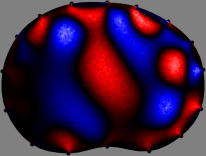

Refer to caption

Figure 2: Fidelity-embedded regularization method. (Left bottom) Correlations between four different column vectors (𝐒ksubscript𝐒𝑘{\bf S}_{k}) and all the remaining column vectors (𝐒subscript𝐒{\bf S}_{\ell}) are visualized. (Right bottom) Performances of the proposed fidelity-embedded regularization method for λ=𝜆\lambda=\infty are shown by numerical simulations.

To explain the FER method, we closely examine the correlations among column vectors of the sensitivity matrix 𝕊𝕊\mathbb{S}, described in Fig. 2. The correlation between 𝐒ksubscript𝐒𝑘{\bf S}_{k} and 𝐒subscript𝐒{\bf S}_{\ell} can be expressed as

for i=1,,16𝑖116i=1,\cdots,16[23]. This shows that the column vector 𝐒ksubscript𝐒𝑘{\bf S}_{k} is like an EEG (electroencephalography) data induced by dipole sources with directions uj,j=1,,16formulae-sequencesubscript𝑢𝑗𝑗116\nabla u_{j},j=1,\cdots,16 at locations ΔksubscriptΔ𝑘\Delta_{k}. Given that two dipole sources at distant locations produce mutually independent data, the correlation between 𝐒ksubscript𝐒𝑘\mathbf{S}_{k} and 𝐒subscript𝐒\mathbf{S}_{\ell} decreases with the distance between ΔksubscriptΔ𝑘\Delta_{k} and ΔsubscriptΔ\Delta_{\ell}. Fig. 2 shows a few images of the correlation 𝐒k,𝐒(|𝐒k||𝐒|)1subscript𝐒𝑘subscript𝐒superscriptsubscript𝐒𝑘subscript𝐒1\left\langle\mathbf{S}_{k},\mathbf{S}_{\ell}\right\rangle(|\mathbf{S}_{k}||\mathbf{S}_{\ell}|)^{-1} as a function of \ell for four different positions ΔksubscriptΔ𝑘\Delta_{k}. The correlation decreases rapidly as the distance increases. In the green regions where the correlation is almost zero, 𝐒subscript𝐒{\bf S}_{\ell} is nearly orthogonal to 𝐒ksubscript𝐒𝑘{\bf S}_{k}.